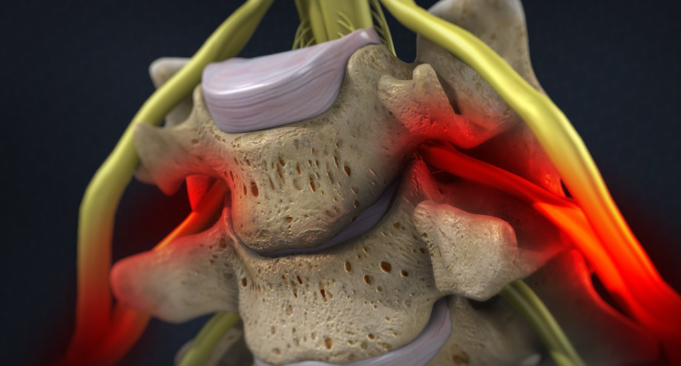

1.2 경추 추간판 탈출증

이 상태는 디스크의 내부 젤 같은 핵이 외부 섬유층의 찢어진 틈을 통해 돌출되어 잠재적으로 신경을 압박하고 통증이나 신경학적 증상을 유발할 때 발생합니다.